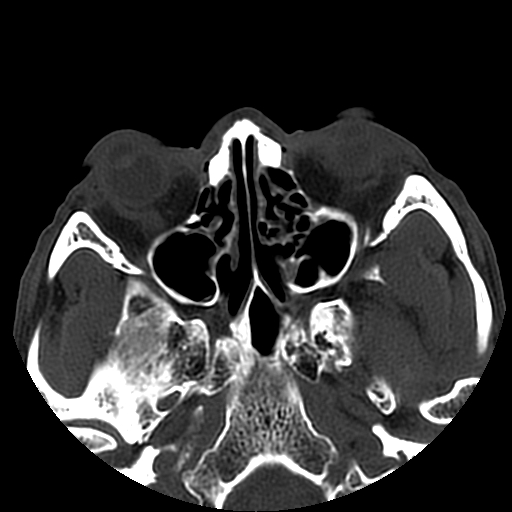

以下是引用liaoqiang在2008-7-16 21:15:00的发言:[br]右侧鼻骨骨折

以下是引用zxd95在2008-7-16 21:39:00的发言:[br]右侧上颌骨额突骨折。[br][br][br][br]